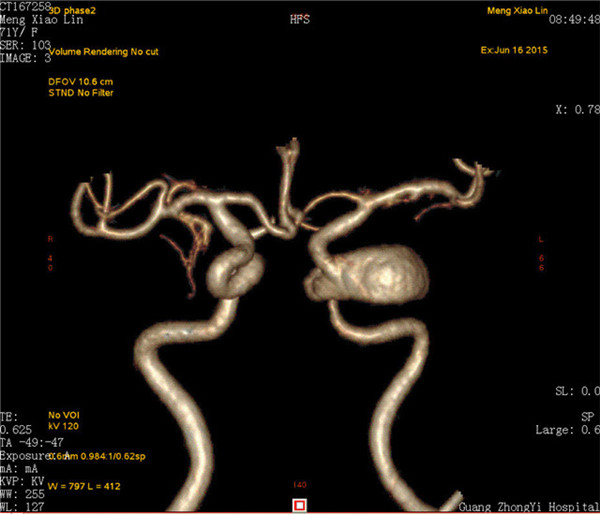

患者是一位70岁的女性,已视物重影1年余,经外院检查确诊为“左侧颈内动脉海绵窦段巨大动脉瘤伴瘤内血栓形成”,医生告知因动脉瘤位于海绵窦内,瘤颈宽约8mm,大小约2.8×2.3×2.2cm,传统手术方法无法完成动脉瘤夹闭或栓塞治疗,同时手术创伤大、风险高。听了医生的话患者不得不放弃手术。

最近,患者因症状加重来到Beat365中国唯一官方网站第一附属医院求治。该院神经外科张高炼主任主持的治疗团队对该病例进行了讨论和分析,因影像学检查显示动脉瘤载瘤动脉明显迂曲且血管直径较细小,覆膜支架系统通过可能较困难且易引起载瘤血管损伤或动脉瘤破裂出血,他们决定利用密网支架技术行颅内巨大动脉瘤封堵技术为患者治疗。新技术的开展经汇报后得到院领导的大力支持,医院为此简化医疗药械申购手续,购买由美国eV3公司生产的Pipeline血流导向装置(密网支架系统),并邀请到中美合作上海德济医院院长宋冬雷教授前来会诊和指导。

术前CTA